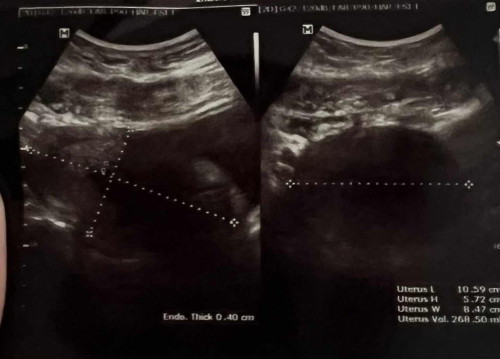

กี่วิคแล้วคะถ้า7/8วิคแล้วยังไม่พบเด็กอาจเป็นท้องลมได้คะวัดขนาดส่วนในมดลูกแล้วดูโลงเหมือนที่เราเคยเป็นคะ

น่าจะวัดขนาดโพรงที่น้องอยู่นะคะ